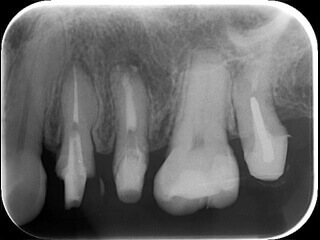

症例1 神経を取っても痛みが取れない

2

膿を出す目的で根管が開放(ガイドラインでは推奨されていません)がされていました。

3

ホルマリンと思われる強い刺激臭がします。

4

綺麗に治療されているように見えます。

5

感染(虫歯など)のみに色がつく染色液です。神経は取れていますが、感染が残ってしまい痛みが残っていました。

6

虫歯を除去し再度バイ菌が入らないよう壁を作ると痛みは無くなりました。(隔壁と言います)